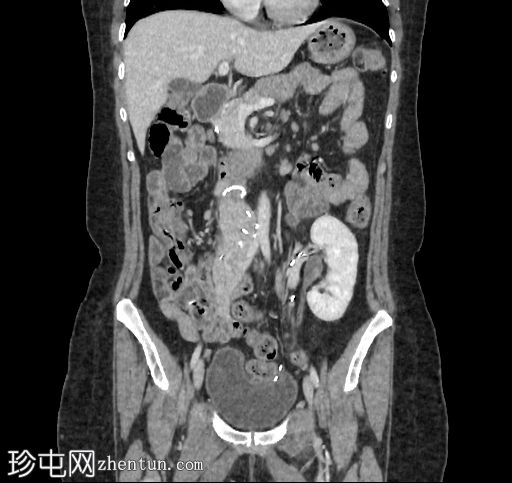

冠状位增强扫描

门静脉期

移植的胰腺位于右侧腹膜后间隙,大小和形态(轴位、冠状位和矢状位)均正常,可见相关手术缝合线。供体十二指肠段与自体十二指肠吻合。可见胰腺移植物与右髂血管的动脉吻合,胰腺实质强化均匀,提示移植物灌注良好。

左髂窝肾移植(轴位、冠状位),显示移植肾与同侧髂总血管的动脉和静脉吻合。移植肾形态完整,实质均匀强化。

本例中,影像学检查显示原位肾脏和胰腺明显萎缩,符合长期糖尿病合并慢性肾脏病的表现。肾移植位于左髂窝,与同侧髂血管的动脉和静脉吻合通畅,肾实质均匀强化,这些影像学表现均符合功能性肾移植的影像学特征。移植胰腺位于右侧腹膜后,形态和位置均符合原位胰腺,供体十二指肠袢与原位十二指肠吻合良好。